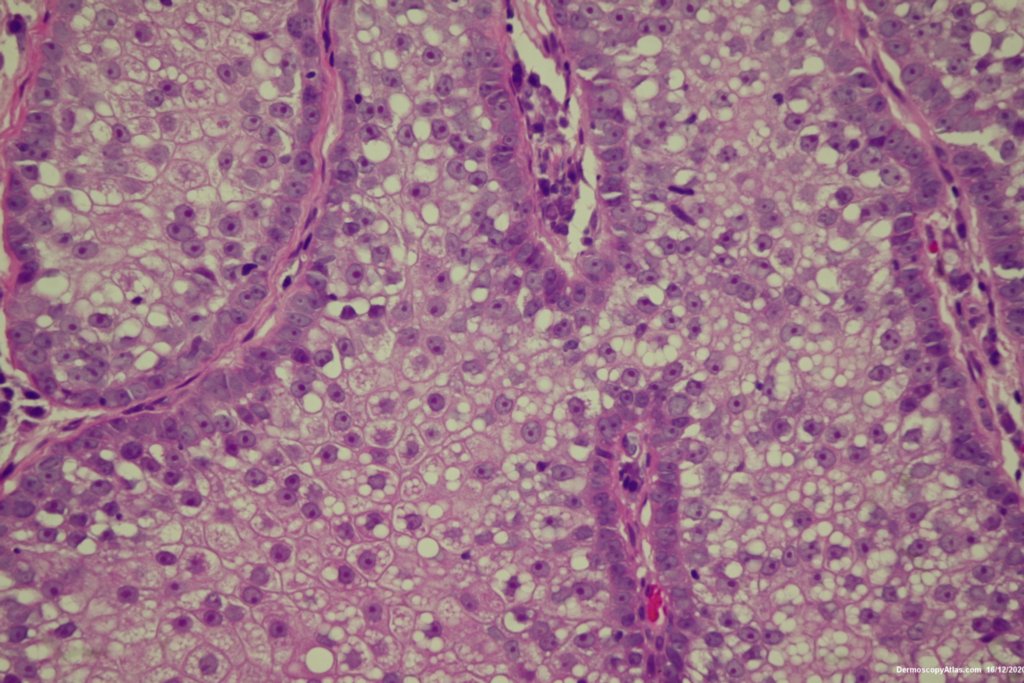

Site: Cheek

Diagnosis: Lentigo Maligna

Description: Pigmented lesion cheek and pink nodule

Elderly male with no past history of melanoma developed these two lesions over a year or so. The lentigo maligna was easy to diagnose on the clinical and dermatoscopy but the nodule was more difficult. Was it an amelanotic melanoma, BCC or SCC were the initial thoughts. Histology showed a well differentiated sebaceous carcinoma. The two lesions were excised in the same specimen with 5 mm margins. Studies failed to show the mutation for the Muir Torre syndrome which can be seen with sebaceous carcinoma.